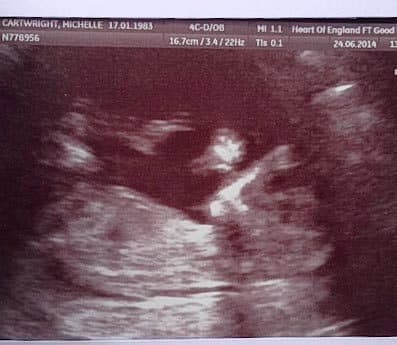

Gracias al accidente que le ocurrió mientras estaba embarazada ahora está con vida.

A la mujer, de 32 años, le dieron estas noticias seis semanas después del evento.